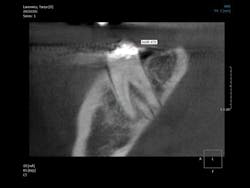

General dentists accomplish the vast majority of endodontic treatment in the United States. This treatment is reported to be the third most frequent use of cone beam. Endodontists, who are the leaders and teachers for endodontic treatment, are now using cone beam routinely. What are some of the reasons for this use? All of us occasionally have a patient with an endodontically treated tooth that appears on a 2-D radiograph to have received excellent endodontic treatment, but the patient still has discomfort. You know the various potential reasons for this treatment failure, but can you visually determine them? Is the tooth cracked? Is there another root or another canal that you cannot see on a 2-D image? Do overlapping roots disguise a problem or condition that could easily be seen on a 3-D image (figures 4-6)? It is easy to predict that cone beam will soon become recognized as being necessary for predictable endodontic diagnosis and treatment.

Figures 4-6: These images provided by Dale Miles, DDS, MS, show a lower right second molar with multiple roots. It is apparent that a 2-D view would be inadequate to provide enough information for appropriate endodontic treatment.